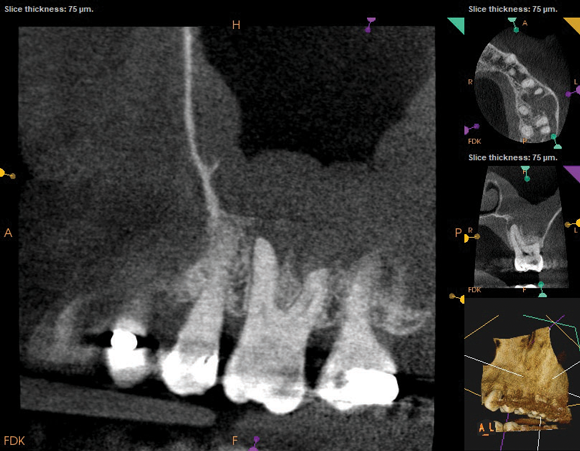

The diagnosis for tooth No. 14 was pulpal necrosis with asymptomatic apical periodontitis. NSRCT was completed (Figure 9), followed by full-coverage restorative care performed by the general dentist. A 3-month follow-up revealed resolution of prior sinus symptoms, normal clinical findings, and healing radiographic pathology, including periapical pathology and associated maxillary sinus mucositis (Figure 10 and Figure 11).

Fig 10. CBCT imaging at 3-month follow-up showing signs of healing and decrease in maxillary sinus mucositis. Fig 10: Sagittal view, buccal roots No. 14. Fig 11: Sagittal view, palatal root No. 14.

Figure 10

Fig 11. CBCT imaging at 3-month follow-up showing signs of healing and decrease in maxillary sinus mucositis. Fig 10: Sagittal view, buccal roots No. 14. Fig 11: Sagittal view, palatal root No. 14.

Figure 11